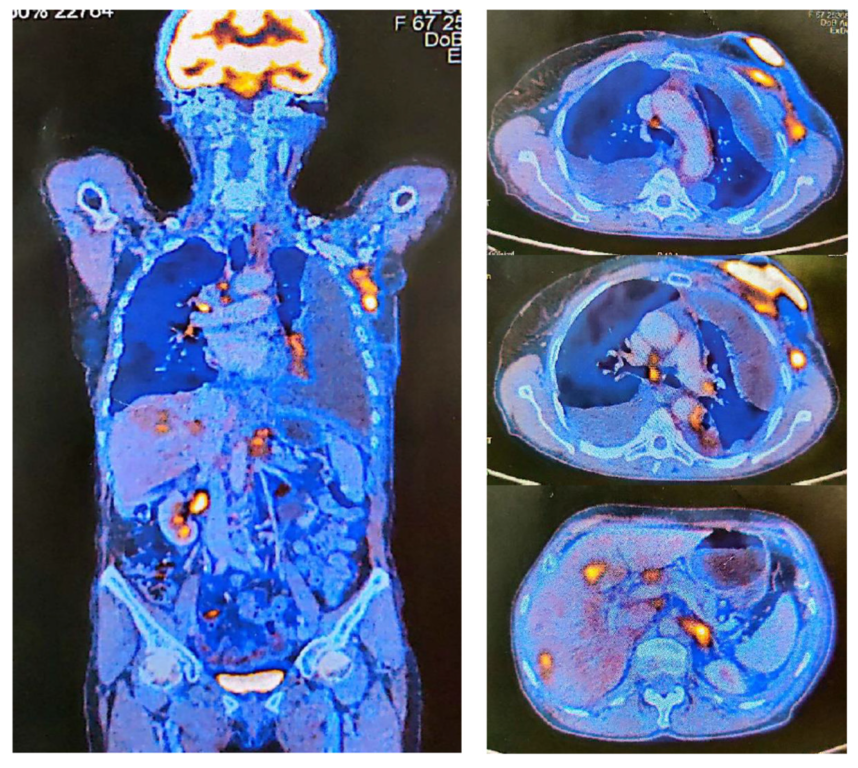

| PET-CT | Positron Emission Tomography |

| SUV | Standardized Uptake Values |

| M1HEP | Hepatic metastases |

| M1LYM | Lymphatic metastases |

| M1ADR | Adrenal metastases |